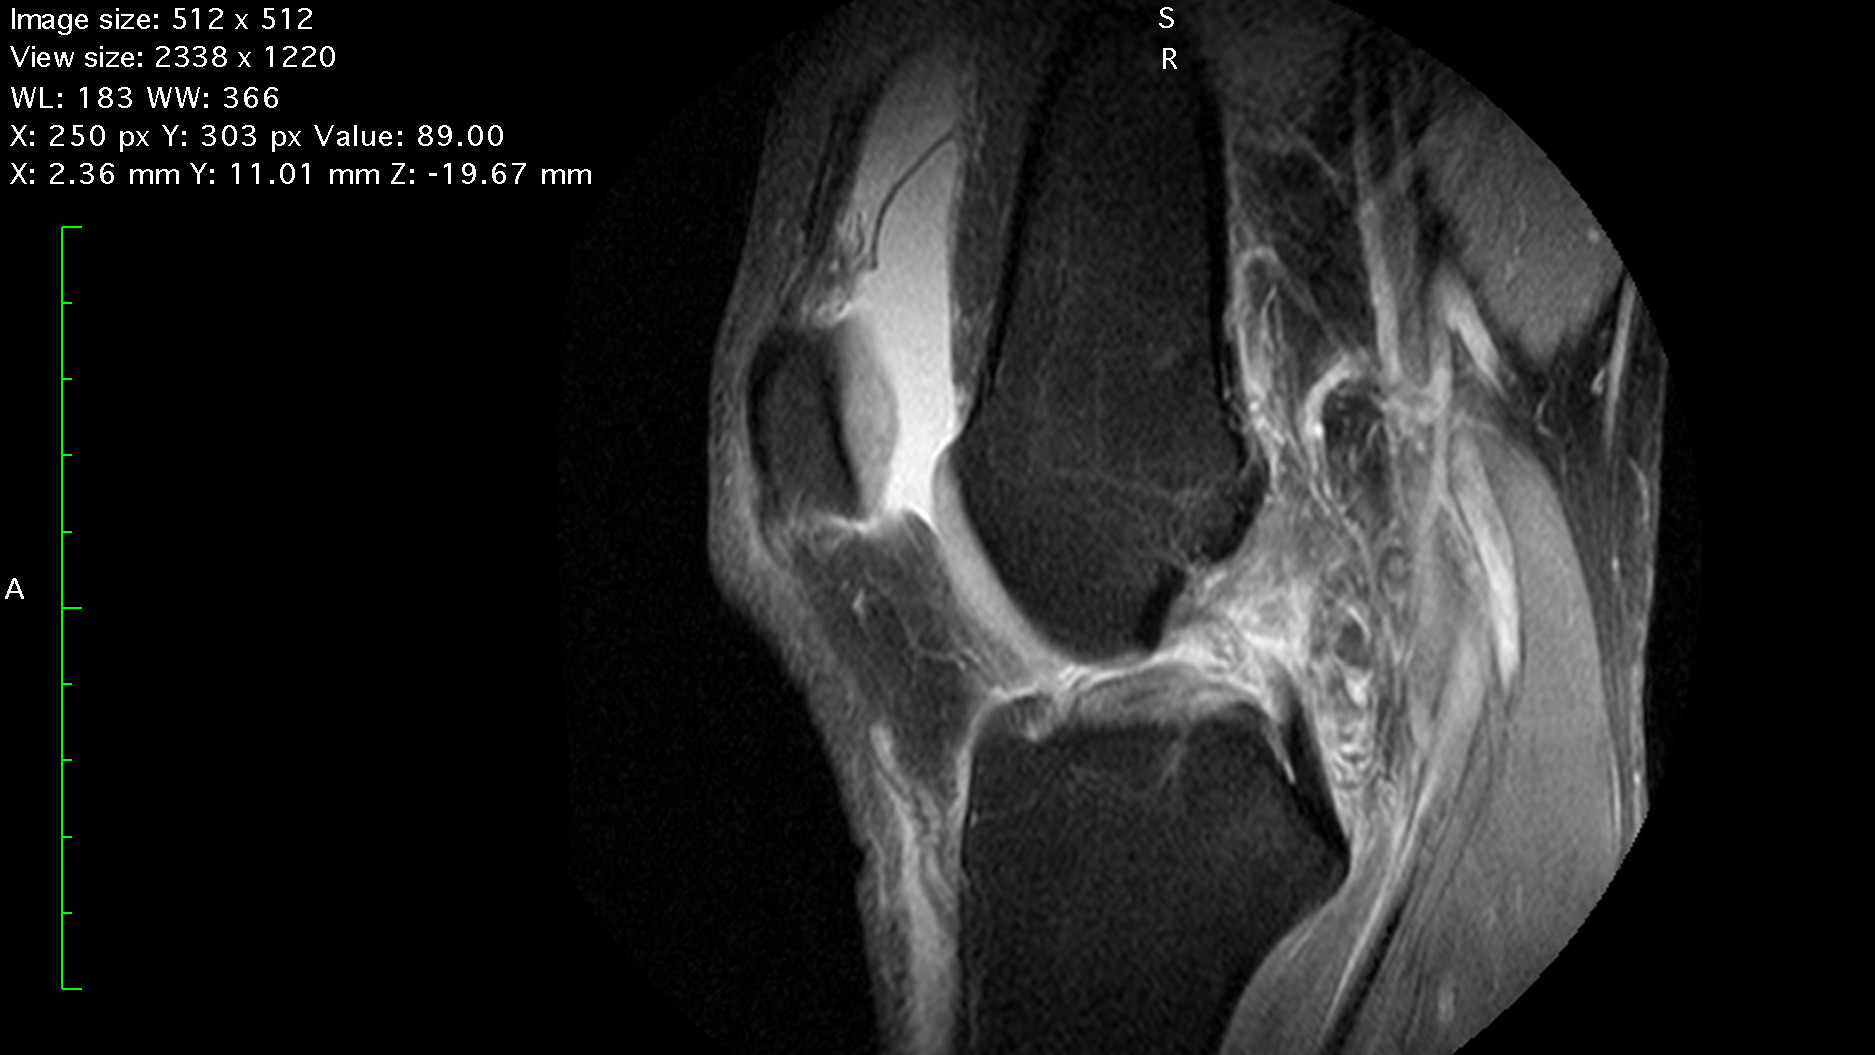

The ACL Diaries: A skier's journey from ACL Tear to recovery - Pt.1 - Heartbreak